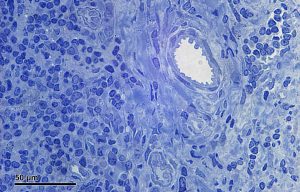

Tonsils (Figure 21.7) Tonsils are large non-encapsulated (or partially encapsulated) masses of lymphoid tissue. They can be found in the pharynx or nasopharynx and at the base of the tongue. The superficial part of the tonsils are covered with a stratified squamous epithelium. Tonsils have many invaginations which form blind crypts. Below the epithelium, there are many lymphoid follicles beneath which have germinal centers.

Figure 21.7 Human tonsil microanatomy. Credit: Dr. Josef Reischig, Wikimedia Commons, license CC-BY-SA 3.0

3. Tonsils are lymphatic nodules. They are located in the oral cavity and pharynx. The tissue is broken up by a number of crypts. These are deep infolding tissue. Tonsilar nodules are made up of large number of lymphocytes. Germinal centers are light in color and surrounded by lymphocytes that are deep blue.

4. Select different regions of the tonsil and observe under high power.

5. Take a picture of your observations at low power and high power, paste the picture below and label the main structures and cell types observed.